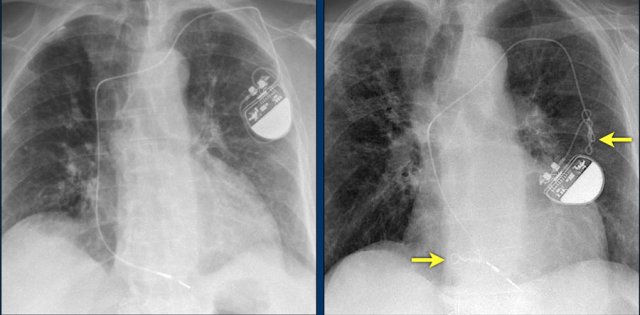

Here a patient with a normally placed ICD on the left image.

Months later there was malfunction due to ICD box and lead rotation (yellow arrow) and retraction (white arrow).

Here another patient with the Twiddler's syndrome.

Notice curling of the lead near the pacemaker and at the tip in the right ventricle (arrows).